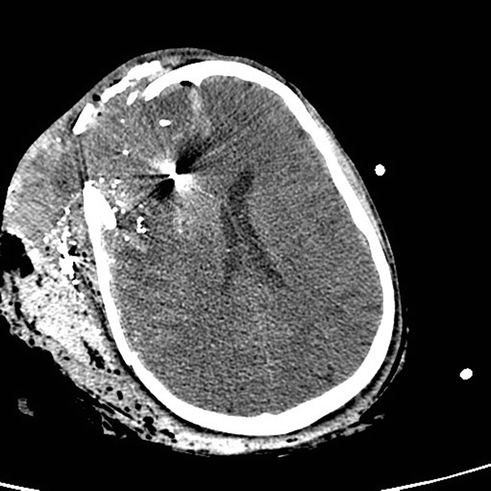

Fig. 19.3

Sagittal CT showing extension of the craniectomy posterior to the coronal suture

A 21-year-old male was involved in a T-bone collision while riding a motorcycle wearing a full face helmet. He was a GCS 3T on arrival to the hospital. His head injuries involved a left parieto-occipital contrecoup contusion and subtle bifrontal hypodensities and multiple orthopedic injuries. An EVD was placed and his intracranial pressures were managed medically for the first 5 days. Eventually the right parieto-occipital contusion and bifrontal hypodensities evolved causing 5 mm of left to right midline shift and medically refractory elevated ICPs > 20 mmHg. A wide bifrontal craniectomy was performed. He developed bilateral subdural hygromas 2 weeks after surgery that resolved spontaneously after 3 days of observation. He underwent a bifrontal cranioplasty 4 months after the craniectomy. He was discharged to neuro-rehab with a GCS 14. He has moderate cognitive changes and emotional lability consistent with his frontal lobe injury.